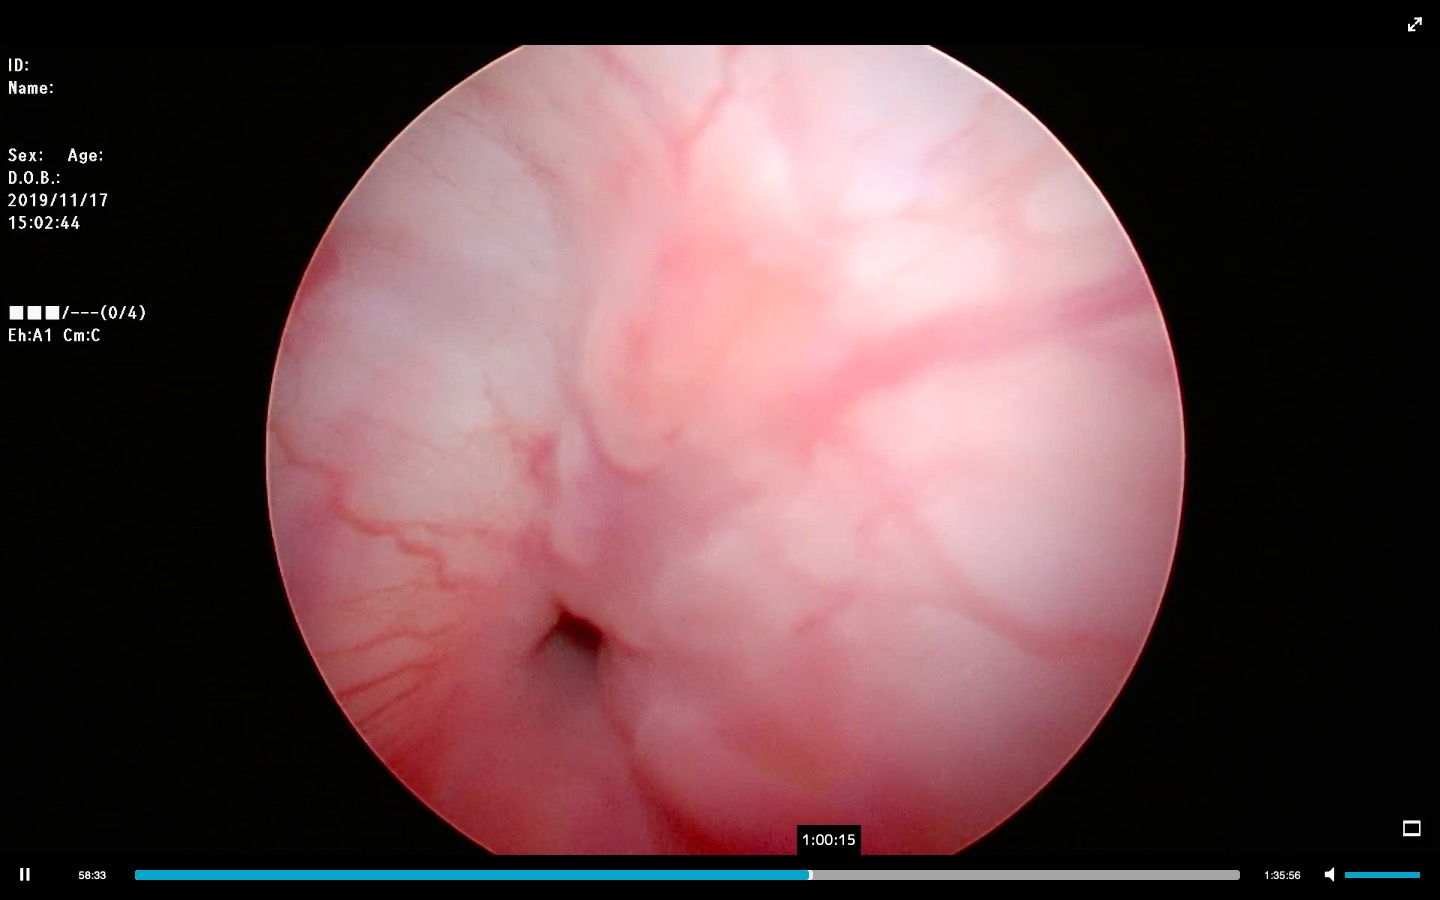

第一ポートにトロッカーを設置している写真です。

腹腔鏡とは腹壁にカメラが入るサイズの小さい傷を作り、トロッカーと呼ばれる機械を挿入します。(第一ポート)

これが傷の穴を広げてくれるので腹腔鏡カメラを挿入しやすくなります。

トロッカーより腹腔内にまずガスを入れ、頭側の視野を広げます。十分に気腹(ガスをいれること)ができたらカメラで確認しつつ、トロッカーの挿入時に他の臓器を傷つけず、安全に第二ポートが設置できる場所を決定します。